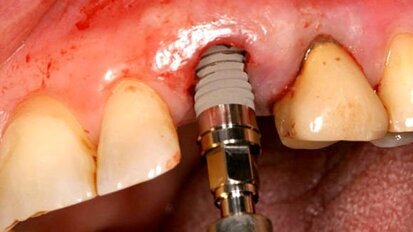

На 8 и 9 ноември 2014 г. в Атина предстои двудневен теоретично-практически курс по ...